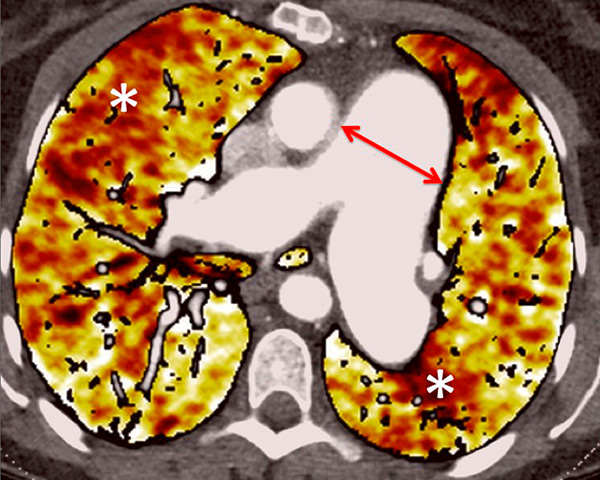

Figure 6

Perfusion heterogeneities in idiopathic pulmonary artery hypertension (stars) in two different patients (A/B). The dilatation of the arteries in pulmonary hypertension (arrows) is not always observed depending on the severity of pulmonary hypertension.